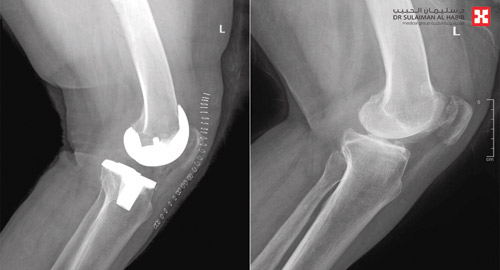

«ستينية» تستعيد القدرة على المشي بمستشفى الدكتور سليمان الحبيب بالسويدي

استعادت سيدة «ستينية» قدرتها على المشي، وتخلصت من الكرسي المتحرك، بعد ساعات من عملية نوعية لاستبدال مفصل ركبة، خضعت لها في مستشفى الدكتور سليمان الحبيب بالسويدي، بتقنية تخفف الآلام وتسرع التشافي، أنهت معاناتها مع الخشونة والاحتكاك الحاد وتلف غضاريف المفاصل، وغيرها من التبعات الحادة. وقال د. رغيد شبو